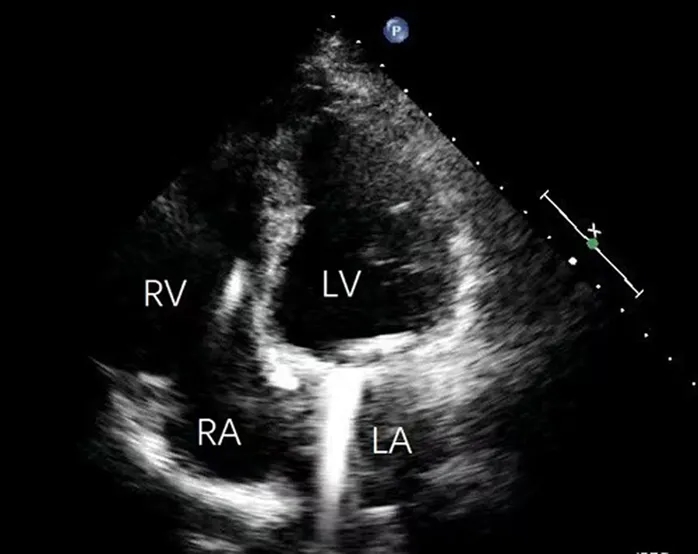

患者于术后第2日拔除气管插管,第3日转出重症监护室,术后第10日顺利出院。出院前经胸超声心动图示:左心室室壁瘤完全消失、心尖形态恢复正常,射血分数为61%,双机械瓣功能良好(主动脉瓣与二尖瓣平均跨瓣压差分别为8mmHg及7mmHg),且无瓣周漏(图7)。

图7 出院前经胸超声心动图

术后6个月随访时,患者心功能维持于纽约心脏病协会分级Ⅰ级(术前为Ⅲ级),日常活动不受限,且未再发生ICD放电。超声心动图显示左心室大小、形态及功能均正常(射血分数:60%),双机械瓣功能良好(主动脉瓣与二尖瓣平均跨瓣压差分别为2mmHg与7mmHg)(图8)。动态心电图监测未见室性心动过速,仅偶发室性早搏。继续华法林抗凝治疗。

图8 术后6个月随访超声心动图